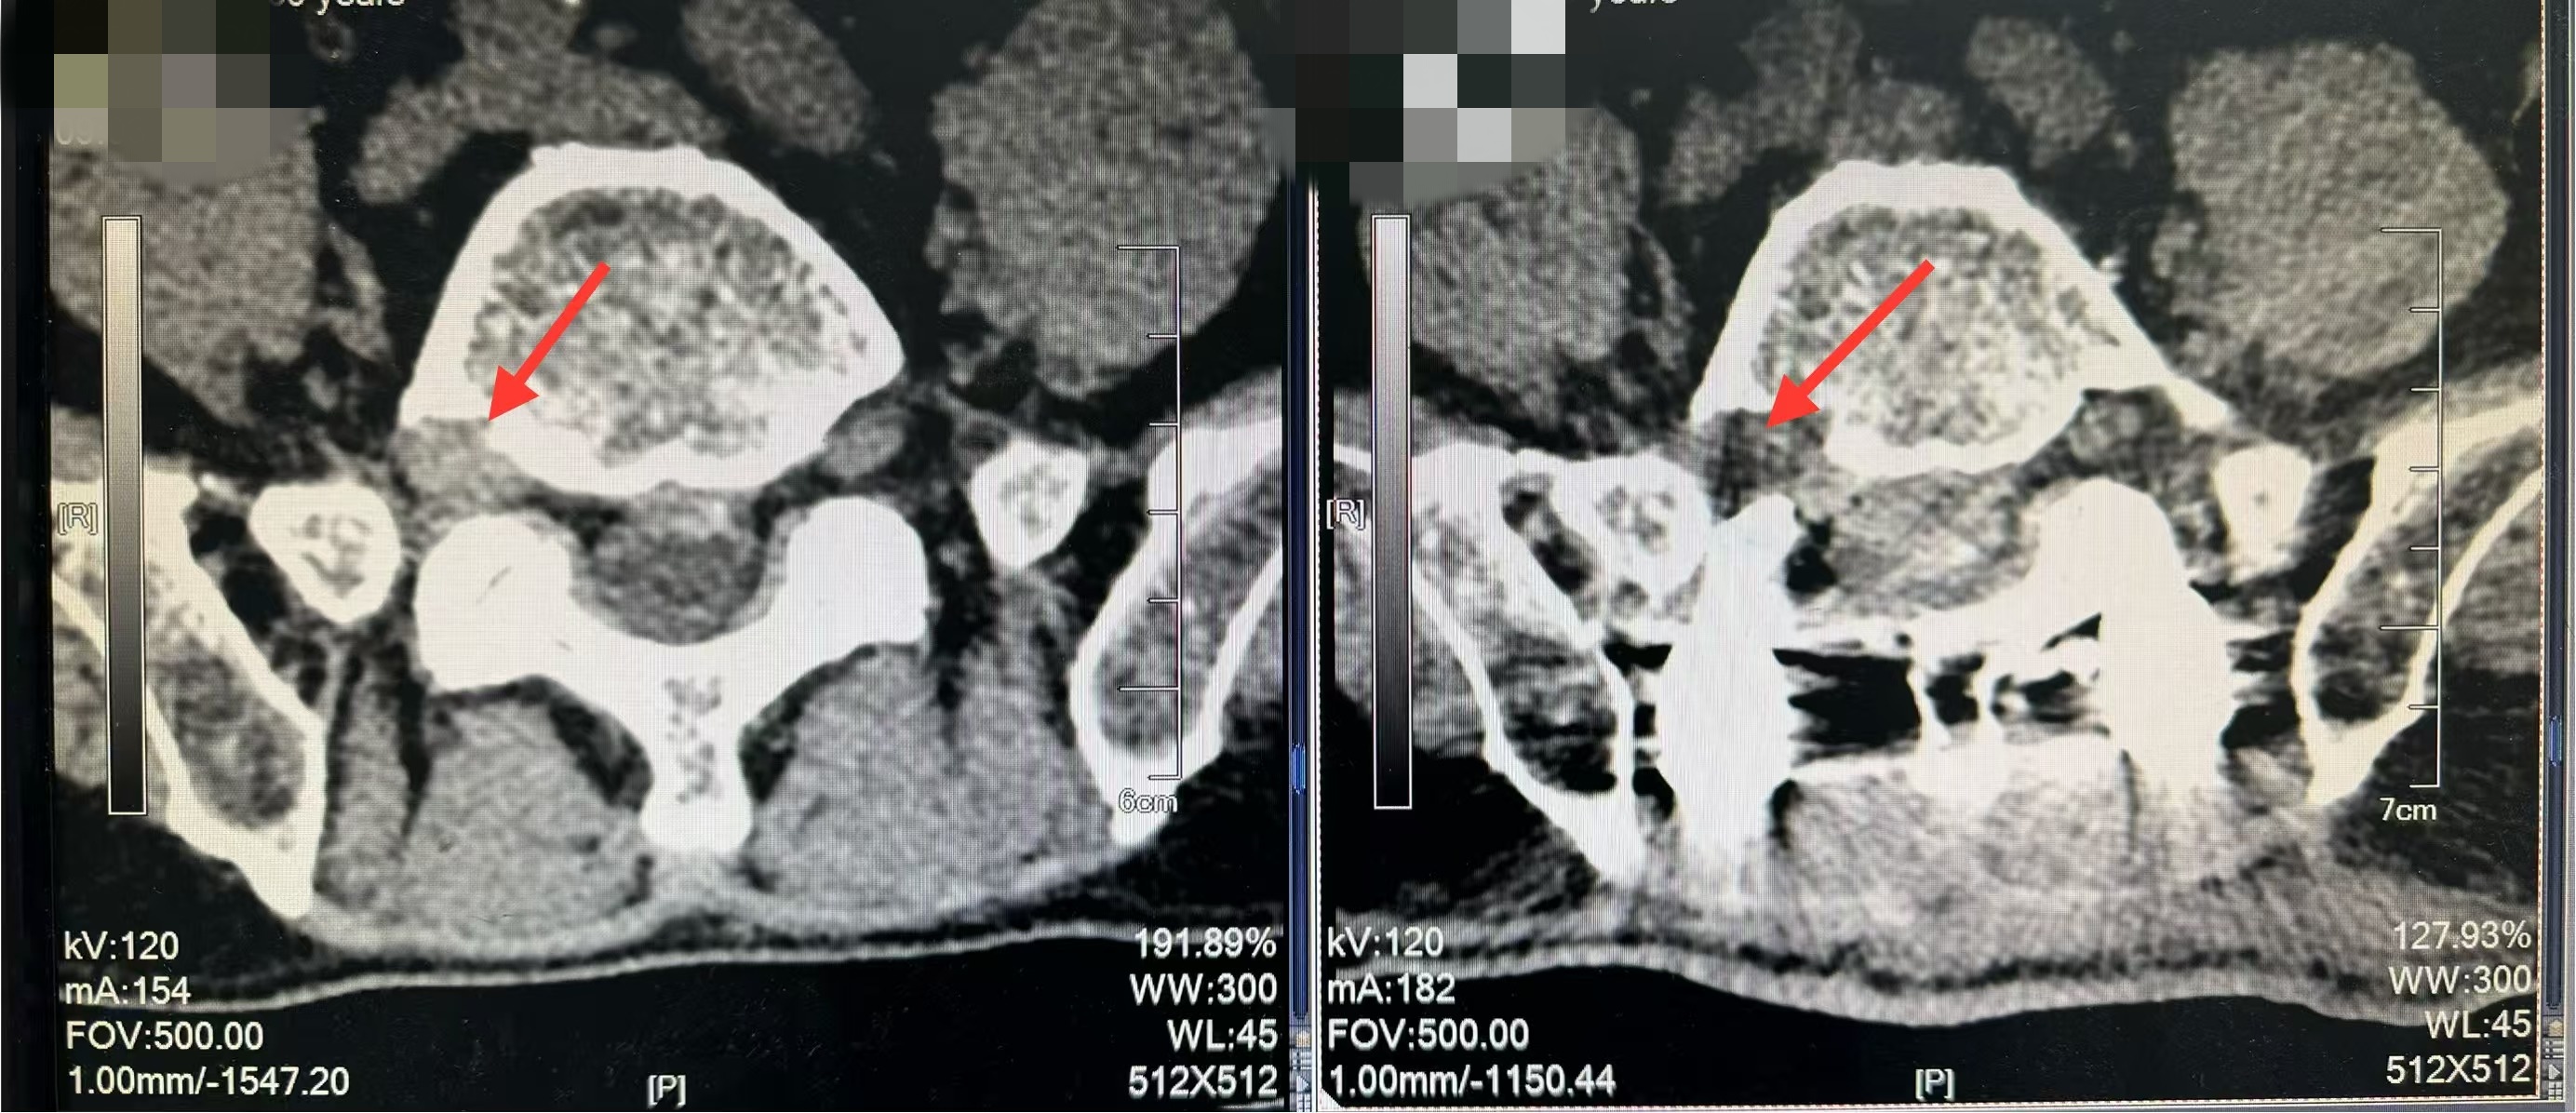

结合详尽的临床检查与影像学分析,细心的殷浩副主任医师发现杨先生的病变竟然是右侧极外侧型椎间盘突出。极外侧型椎间盘突出指脱出的或突出的椎间盘组织位于椎间孔内或孔外,导致同节段的脊神经根受到机械性压迫或炎性刺激,造成下肢放射性疼痛,甚至下肢感觉或功能障碍。这种隐藏在角落的腰椎间盘突出,因为解剖位置特殊,在诊断和治疗方面存在较大挑战。

明确病因后,在手术方式的选择方面,殷医生犯了难。极外侧型椎间盘突出一般适合微创手术,但杨先生已有多次微创失败的病史,又存在节段不稳和严重退变。杨先生既往多次手术,遗留瘢痕组织,且常规后入路手术无法直视处理,使得手术难度进一步增加。慎重考虑后,殷浩副主任医师决定采用微创通道下后外侧入路腰椎后路融合固定术+椎间盘摘除、神经根黏连松解术,这种手术方式对杨先生来说,突出节段固定更为牢固、稳妥。这一合理决策得到了骨科五病区主任贺学军的高度认可,外科手术的核心是根据患者实际情况选择适合的技术,微创技术是现代发展的趋势,但使用不同的手术方式在面对复杂病例中仍然具有不可替代的地位,能确保患者的长期疗效。